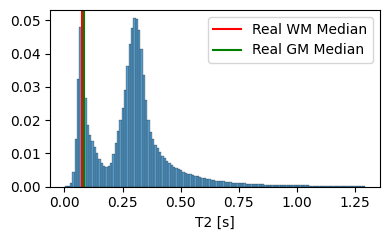

We set and based on the median of the property value distribution measured in real brain tissue [1], corresponding to a log-normal prior with a median of on T1 and a median of on T2.

3.1.2 Analysis of the Tissue Property Distribution

To ensure that our model can extrapolate to unseen modalities, it is crucial that the tissue property maps contain physically plausible values. In Figure 4, we compare the distribution of T1 and T2 values generated by our model to the average T1 and T2 values of white matter and grey matter in actual brain tissue. The results highlight the importance of the prior on the predicted T1 and T2 values, as it guides the model towards generating tissue properties that are, on average, more realistic. However, it is essential to note that the generated distribution includes tissue types beyond white matter and grey matter, such as cerebrospinal fluid and bones.